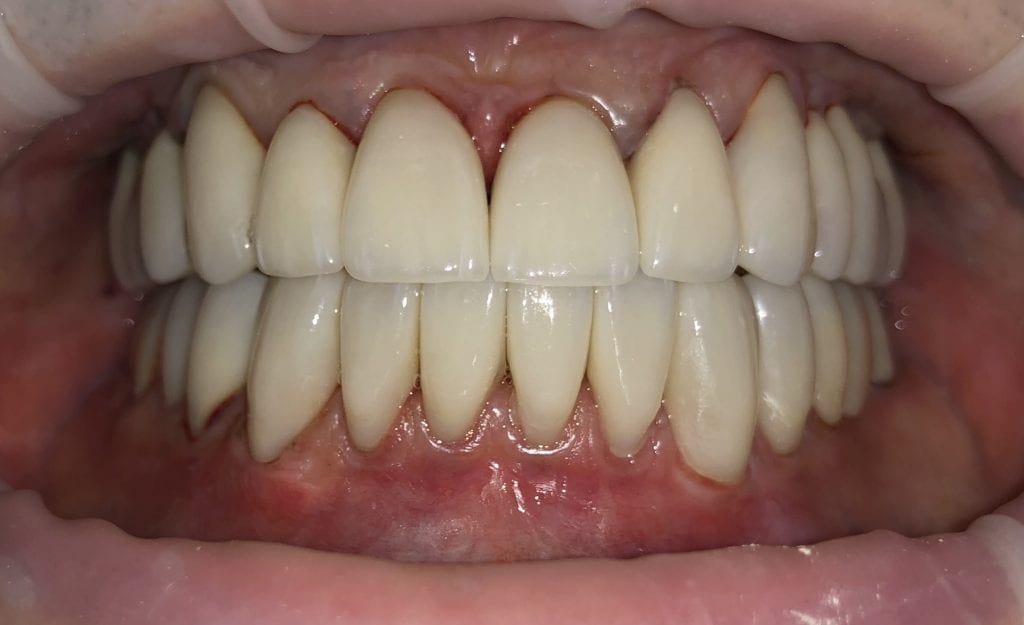

IMMEDIATE POST-OP PHOTOS AND VIDEO WITH IPHONE CAMERA